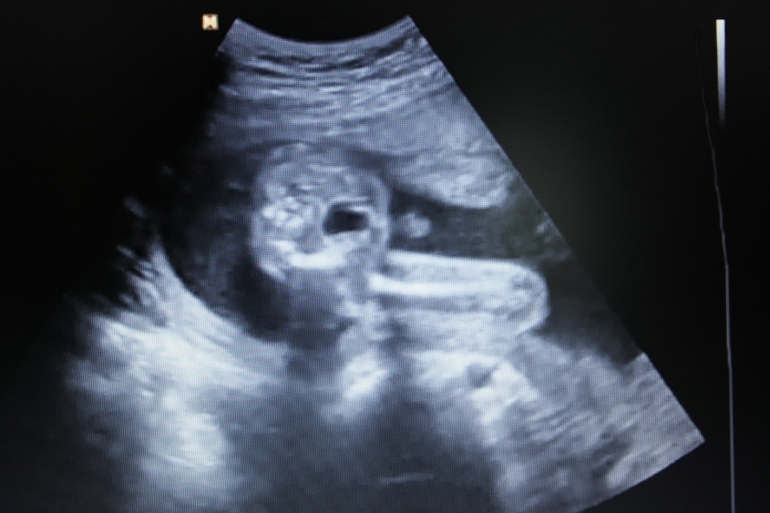

Вид снизу:

еще вот такой ракурс: